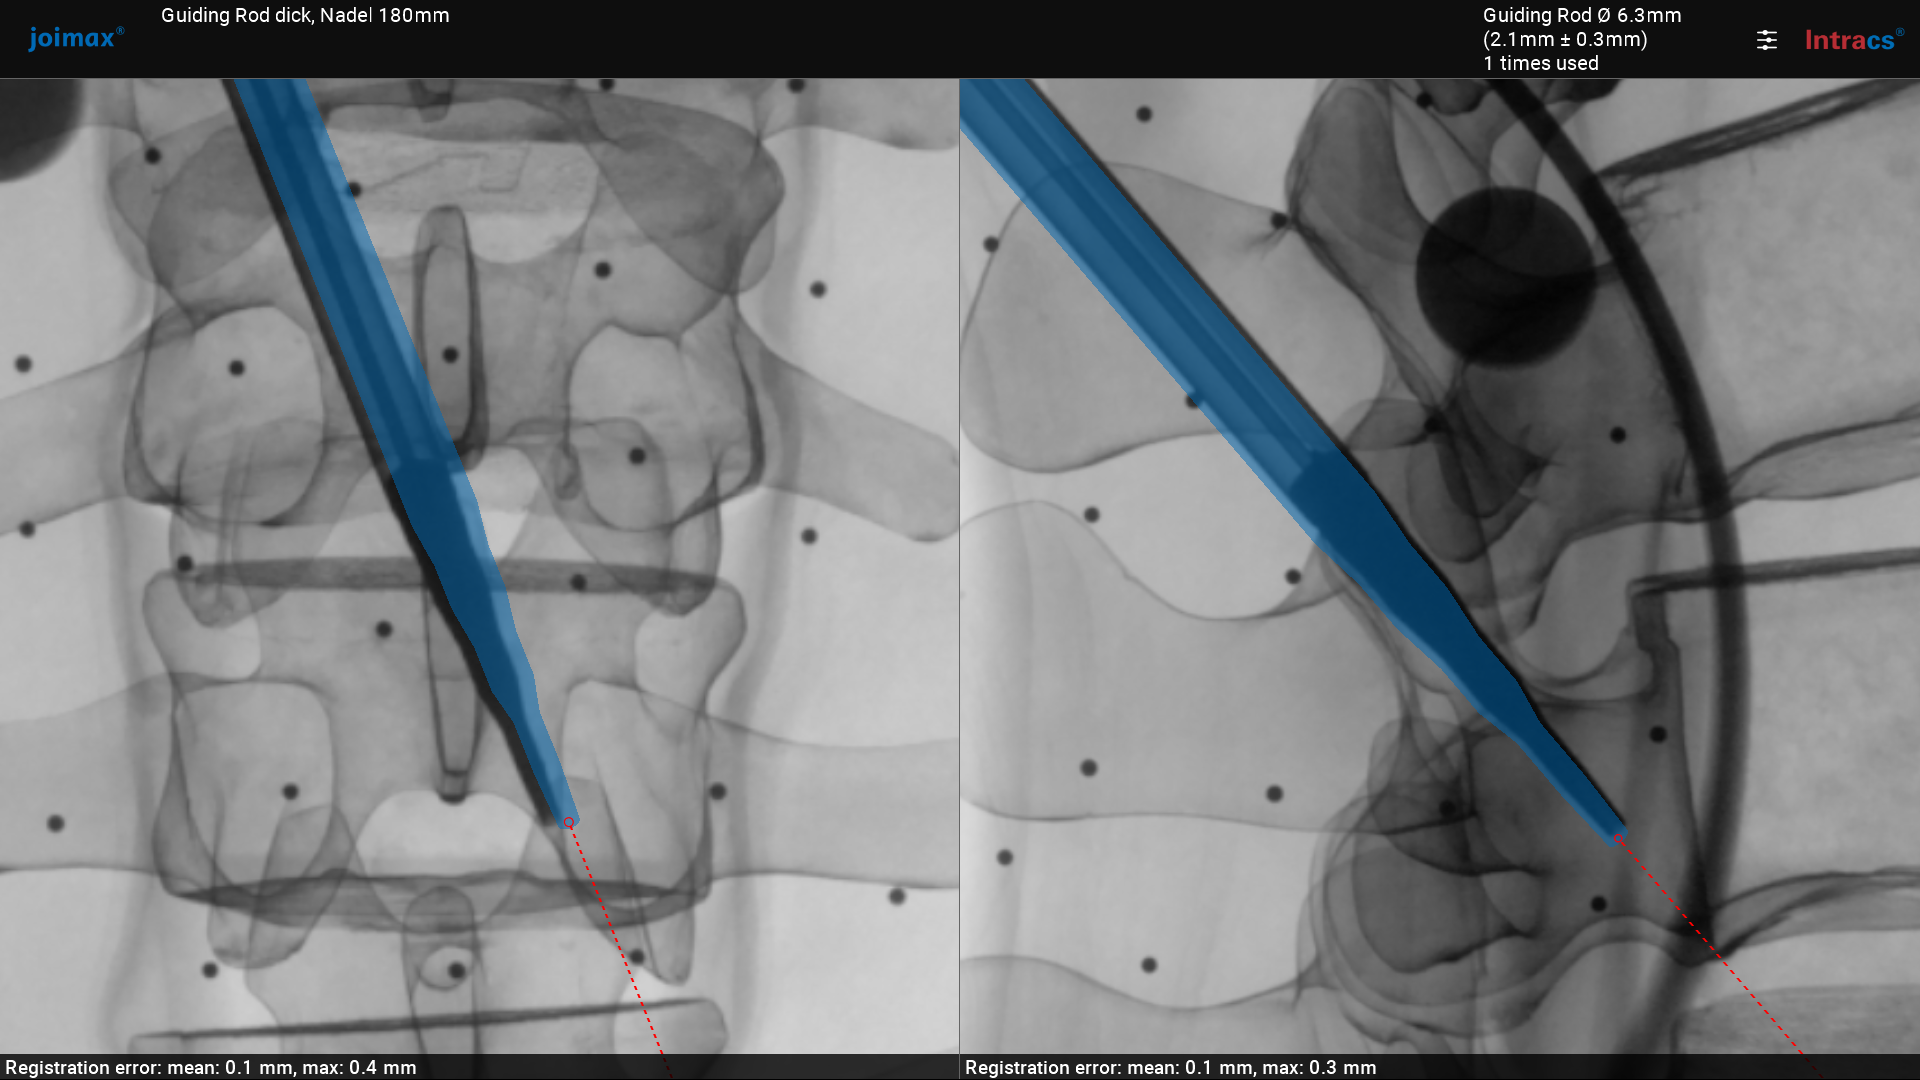

Surgical navigation for 2D (LAT/AP) C-arm-based spinal surgery (2018)

Project: Surgical navigation for C-arm-based spinal surgery

Scientists involved: WW, EL, SH, NS, JZ, BL, BZ, JZ, SS, CS, Tim Lueth

Objective: The objective was to develop a very fast, efficient, and easy-to-use navigation system for spinal surgery. Robust, reusable electromagnetic instruments must be used. The system must offer a way to co-register C-arm projection image data and CT/MRI-based volumetric image data.

Results: The Integrated Navigation Tracking & Control System received the 2019 Spine Technology Award from the North American Spine Society (NASS) in September 2019.

Selection of our publications:

https://www.odtmag.com/contents/view_breaking-news/2019-09-23/nass-news-joimax-wins-2019-spine-technology-award/

The system is certified and in regular clinical use worldwide.